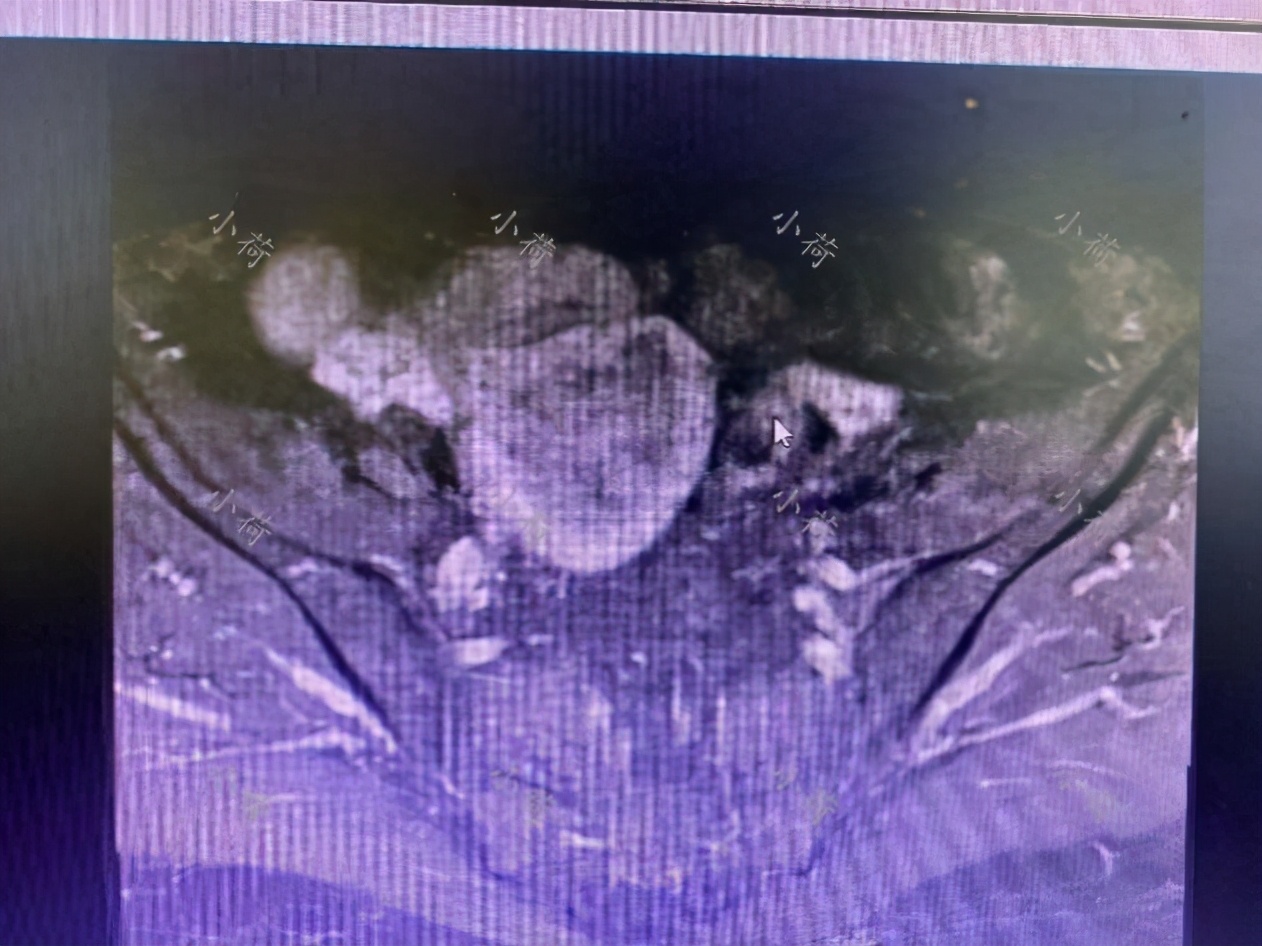

患者行盆腔磁共振检查,回报为:符合子宫内膜癌改变(ⅠB期),盆腔未见肿大淋巴结(图3)。

图3 盆腔磁共振检查显示符合子宫内膜癌改变,盆腔未见肿大淋巴结